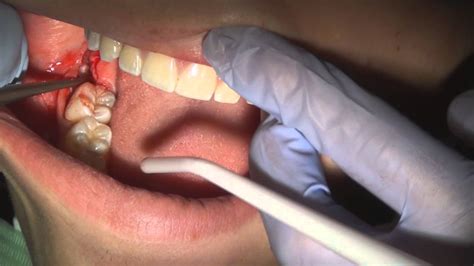

Soft Tissue Impaction The tooth has broken through the gum but not fully. High risk of infection (pericoronitis).

If your wisdom teeth are emerging slowly and are not causing severe pain, there are several methods to alleviate the temporary discomfort. These practices focus on reducing inflammation and maintaining strict oral hygiene to prevent bacteria from accumulating in the sensitive area.

When to Schedule a Professional Consultation

There comes a point where home remedies are no longer enough. Your dentist will monitor the progression of your wisdom teeth coming in through routine dental X-rays. These images provide a clear view of how the teeth are oriented and whether they are likely to cause future damage to your healthy second molars. You should make an appointment if you experience:

Persistent pain that interferes with eating or sleeping is the most obvious sign, but you should also watch for "referred" pain. Sometimes, wisdom teeth push against neighboring teeth, causing them to shift and creating a ripple effect of misalignment across your entire smile. If your dentist notices that the wisdom teeth are creating a "pocket" where bacteria are gathering, extraction is usually the recommended course of action to preserve the integrity of your surrounding teeth.